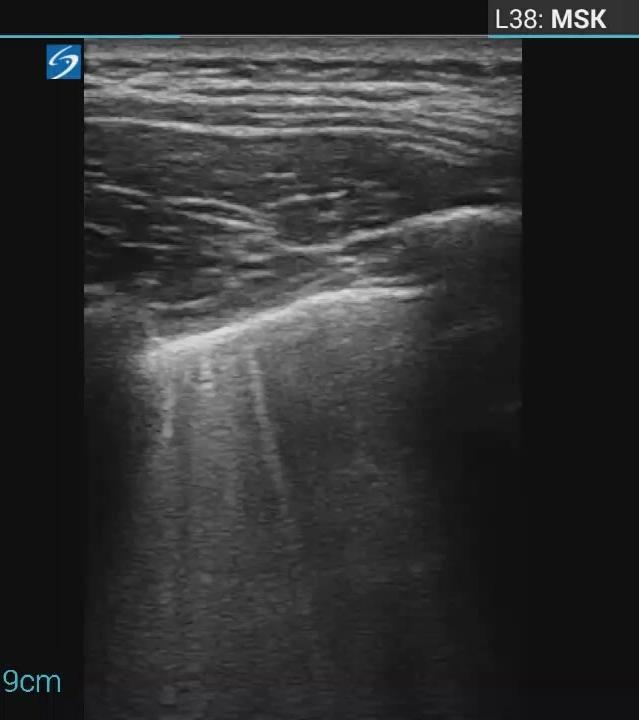

Abdominal abnormalities

Peritoneal abnormalities

Small ascites

Mesenteric abnormalities

Mesenteric lymphadenopathy

• Gastrointestinal (GI) symptoms (abdominal pain, diarrhoea and vomiting) are prevalent in MIS-C

• Abdominal pain in 62%

• Up to 90% any GI symptom

• Anumber of studies have described abdominal imaging findings including ascites, bowel wall thickening and mesenteric lymphadenopathy